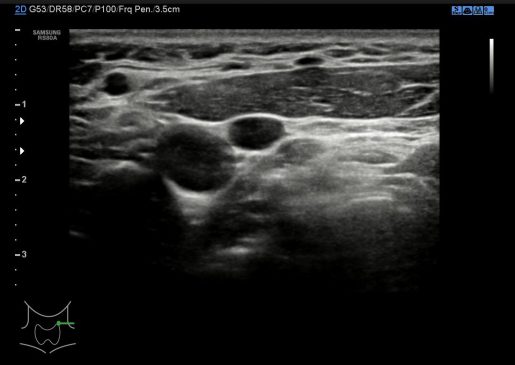

8. Región 1 o Infrauricular (igual que la región 6)

9. Región 2

10. Región 3 o supraclavicular (igual que la región 8)

11. Región 4 Conducto del Tirogloso

Cada región del cuello tiene que tener una foto en el estudio y que puedes ver a continuación, el objeto de esta división es la búsqueda de ganglios locorregionales, así como otros hallazgos extratiroideos que pudieran ser de interés, calcificaciones carotídeas, Tiroides ectópico, incluso las glándulas submaxilares (espacio 1 y 6 pegados al 4) y parótidas (espacio 1 y 6, debajo del pabellón auditivo u oreja).

En condiciones normales no tenemos que encontrarnos hallazgos patológicos, pero es habitual ver ganglios que no deben sobrepasar el centímetro de diámetro en eje corto para ser considerados normales, todos los hallazgos no normales deben ser registrados para posterior evaluación del Radiólogo/a.